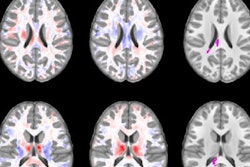

fMRI shows interaction between concussion history and playing position for task-related fMRI BOLD response. Each task level was modeled separately. Clusters with significant interaction (p < 0.001) between concussion history and playing position are overlaid on the Montreal Neuroimaging Institute template brain. Image courtesy of Radiology.Interestingly, the opposite was true for former professional players. Former athletes with one or no concussions had significantly lower fractional anisotropy than players with three or more concussions (p = 0.001). They also had significantly lower BOLD percent signal change across the three working memory tasks (p < 0.001).